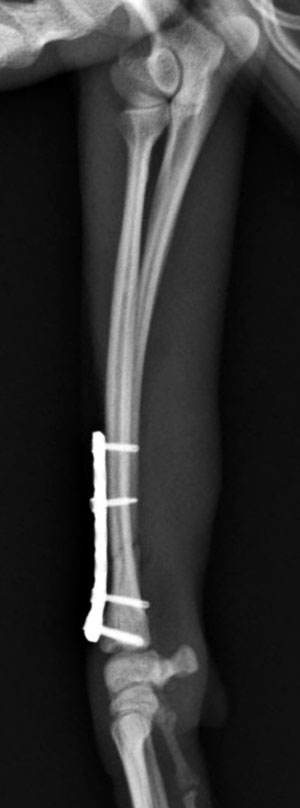

左前腕骨折のトイプードルちゃんの手術がありました。橈尺骨骨折は動物病院では一番よくある骨折です。ロッキングプレートであるTAITANコンディラー1.7mmで対応しました。治りも順調で元気に帰りました。よかったね。